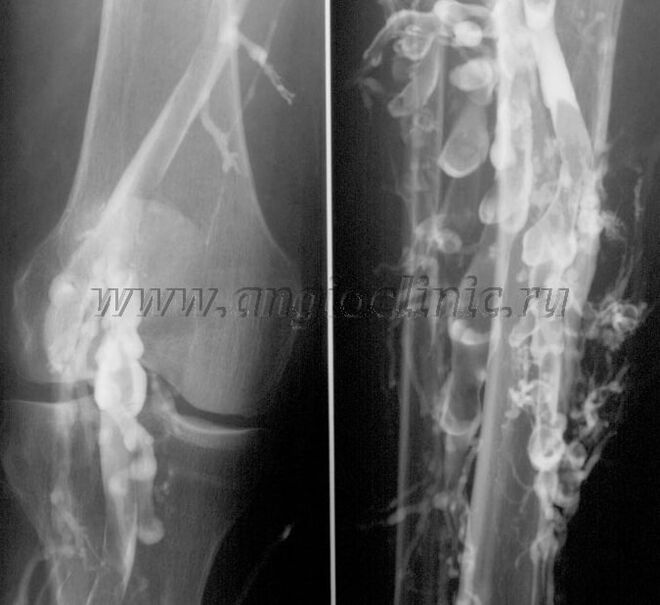

Kontras venografi

Biasana, scanning ultrasound cukup pikeun diagnosis pinuh ku véna Patologi, tapi dina sababaraha kasus perlu pikeun nalungtik hubungan antara kaayaan jero jeung deet sistem véna, utamana dina kasus relapses of varicose urat jeung sekundér varicose urat.

Pikeun ngabéréskeun masalah ieu, pamariksaan sinar-X kontras dianggo. Urat saphenous ditusuk sareng kontras dikaluarkeun. Gerakan kontras dititénan dina monitor mesin sinar-X, sareng sadaya tés sareng unjuran anu diperyogikeun dilaksanakeun. Ayeuna, venography pikeun urat varicose jarang pisan dianggo.